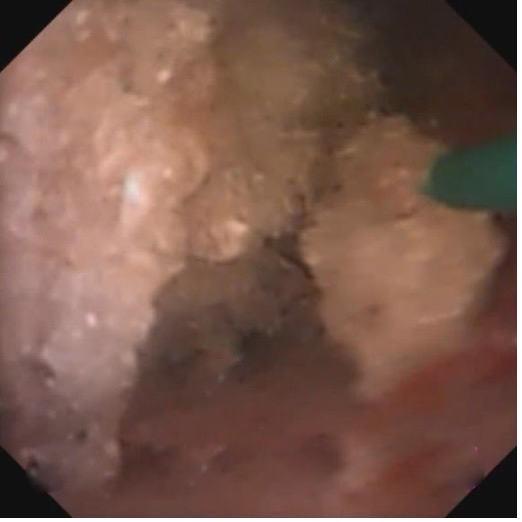

对于小于2-75px的肾结石患者,或者输尿管上段结石采用硬镜无法窥及或者结石上移的患者,则需要在可弯的输尿管软镜下进行碎石手术。该技术同输尿管硬镜手术一样,无需手术切口,恢复快,创伤非常小。本院在福州市内较早引进负压吸引和智能控压设备,确保手术在肾盂内低压状态下完成,同时缩短了手术时间,进而增加了手术的安全性,同时可以将碎石清除率大幅提高。